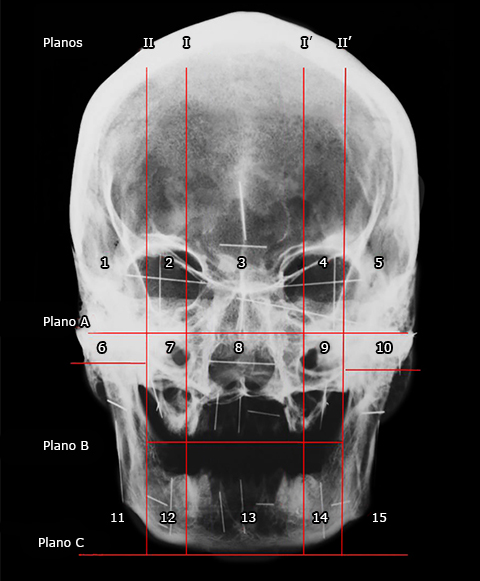

Las figuras 1 y 2 muestran los planos horizontales A, B y C y verticales I, I´, II y II´ en que fueron divididos, tanto el cráneo y la mandíbula (Fig. 1), como las imágenes radiográficas (Fig. 2). Los planos horizontales dividen en tercios cráneo-faciales superior, medio e inferior, en tanto que los verticales delimitan las regiones mediana e intermedias y laterales derecha e izquierda. El plano A pasa por la parte más declive de los bordes infraorbitarios, el plano B pasa por el plano oclusal y se extiende solo hasta el borde anterior de cada ramo de la mandíbula, y el plano C es paralelo al borde inferior del mentón. El plano oclusal es el plano trazado entre los bordes incisales de los dientes incisivos inferiores y las puntas de las cúspides bucales de los molares inferiores; normalmente no es un plano, sin embargo, se le considera el plano medio de la curvatura de estas superficies.(14) Como en el presente trabajo se tenían cráneos y mandíbulas edéntulos, pero se había conservado un espacio intercrestal de 15 mm, se trazó el plano oclusal por la mitad de este espacio. En el tercio superior quedan, esencialmente, las órbitas, la parte superior de la cavidad nasal y la parte superior del cráneo hasta su vértice. En el tercio medio se ubican, principalmente, la parte inferior de la cavidad nasal y la mayor parte de las maxilas. El tercio inferior corresponde, básicamente, a la mandíbula con su cuerpo y ramos.

Fig. 2 - Radiografía posteroanterior de cráneo sobre la cual se han trazado los planos horizontales A, B y C y los planos verticales I, I´, II y II´ empleados para delimitar los 15 cuadrantes en que se dividieron el cráneo y la mandíbula. Igualmente, se muestra la imagen radiológica de los alambres rectangulares de diferente longitud colocados vertical y horizontalmente en cada uno de los 15 cuadrantes.

Los planos I y I’ pasan por el borde más medial de los forámenes infraorbitarios derecho e izquierdo, respectivamente, y los planos II y II’ pasan por el borde anterior de cada ramo de la mandíbula. Quedaron delimitadas, así, la región mediana situada entre los planos I y I`, las regiones intermedias derecha e izquierda situadas entre los planos I y II y los planos I` y II`, respectivamente, y las regiones laterales derecha e izquierda situadas lateralmente a los planos II y II`, respectivamente. Con los tercios y las regiones así delimitados quedaron demarcados 15 cuadrantes que fueron numerados del 1 al 15, sucesivamente de arriba abajo y de derecha a izquierda. Es pertinente aclarar que, dado que el plano B solo se extiende hasta el borde anterior de cada ramo de la mandíbula, en las regiones laterales derecha e izquierda se trazó un pequeño plano horizontal a nivel del borde inferior del arco cigomático con el fin de delimitar cuadrantes laterales medios e inferiores derechos e izquierdos; lo anterior para que los cuadrantes 6 y 10 correspondieran al arco cigomático de cada lado y los cuadrantes 11 y 15 abarcaran todo el ramo de la mandíbula de ambos lados. Esto debido a que en la práctica clínica, el ramo de la mandíbula se considera como una sola unidad cuando se toman medidas en él.